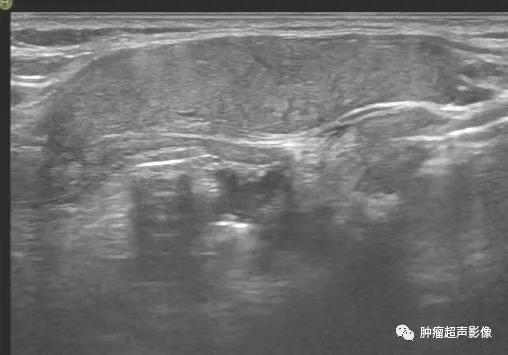

异位甲状腺(迷走甲状腺):正常甲状腺位置未见甲状腺回声,颌下见甲状腺样组织回声,回声不均,血流丰富,类似甲亢表现(推测功能不足,代偿性)